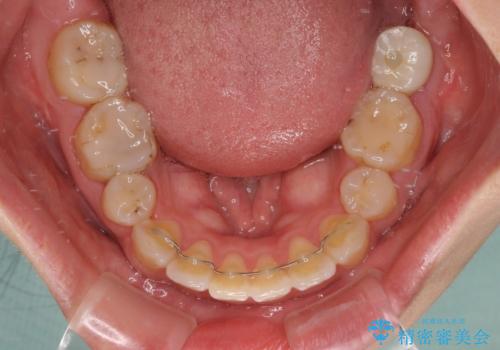

- ハーフリンガル

目立たない装置を希望されたので、上顎が裏側装置のハーフリンガルを選択し、上下左右の小臼歯(計4歯)を抜歯して矯正治療を行うこととしました。

デコボコの解消までは非常にスムーズでしたが、咬合力が強いためか、スペースを閉じるまでに長い期間を要しました。

矯正治療途中にインプラント埋入と仮歯の装着を行ったことで、しっかりとした奥歯の咬み合わせで終了させることができました。